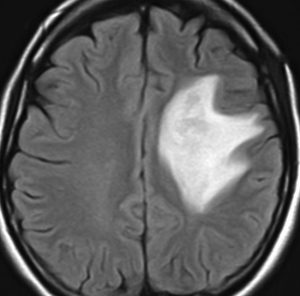

T2-FLAIR mismatch sign (T2とフレアの信号が違うこと)

protoplasmic astrocytomaに特徴的なMRI所見です。T2強調画像(左側)では白く(強い均一な高信号)見えます。でもフレア画像(右側)では白く縁取ったように見えます。びまん性星細胞腫の大きな特徴とされます。内部がとても柔らかいドロドロした腫瘍のこともあります。

mucoid degenerationを含むprotoplasmic astrocytomaの像です。グレード2の典型的病理像です。